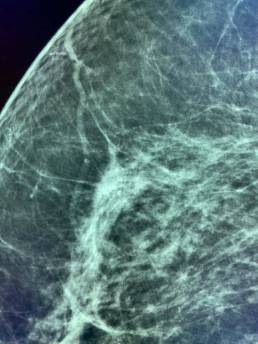

Une femme de 73 ans, mammographie de dépistage. Deux ans avant, sa mammographie de dépistage était considérée comme normale par deux lecteurs.

À première vue, la nouvelle mammographie mammaire a également été considérée comme normale et inchangée par rapport à la précédente, mais MammoScreen a mis en évidence une lésion sur le sein droit.

L’analyse rétrospective de la précédente par MammoScreen a montré la même zone.